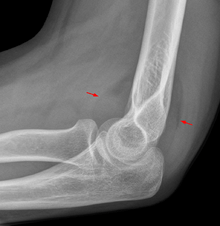

Fat pad sign: Ventral fat pad bowed and dorsal fat pad visible in a case of an undisplaced fracture of the radius head which is not visible directly.

On an elbow X-ray, the fat pad sign, also known as the sail sign, suggests an occult fracture. Its name derives from the fact that it has the shape of a spinnaker (sail).[1] It is caused by displacement of the fat pad around the elbow joint. Both anterior and posterior fat pad signs exist, and both can be found on the same X-ray.

In children, a posterior fat pad sign suggests a condylar fracture of the humerus. In adults it suggests a radial head fracture. The fat pad sign only occurs after an intra-articular fracture.

The fat pad sign is invaluable in assessing for the presence of an intra-articular fracture of the elbow. An anterior fat pad is often normal. However a posterior fat pad seen on a lateral x-ray of the elbow is always abnormal. The patient will be unable to flex their elbow and requires orthopaedic input.[2]